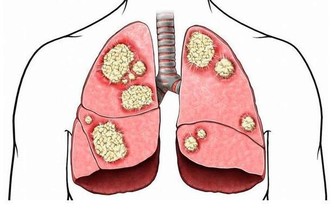

5. 健康問題

如果你睡眠很好、堅持鍛煉、吃得健康,並且壓力有限,但仍然總是很累,那麼最好去看看醫生。

因為下列疾病可以導致過度疲勞:貧血、焦慮症、慢性疲勞綜合症、抑鬱、糖尿病、食物不耐受、心髒病、營養素缺乏症、甲狀腺功能減退症、懷孕、尿路感染等。